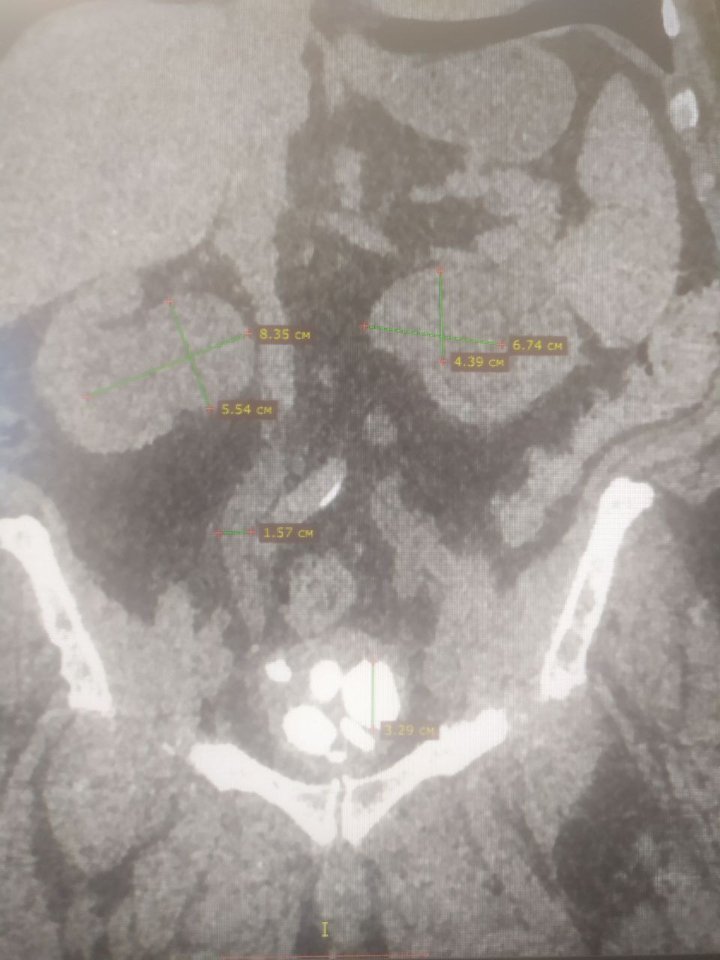

74-річного чоловіка госпіталізували у важкому стані. Лікарі діагностували низку хвороб, частина з яких у запущених стадіях: доброякісна гіперплазія передміхурової залози, хронічна затримка сечі, множинні камені сечового міхура, двобічний уретерогідронефроз, гостра ниркова недостатність.

Першим етапом виконано цистолітотомію з епіцистостомією. Пацієнту забезпечили відтік сечі через спеціальну трубку, адже природній спосіб уже був неможливий. Далі лікарі приступили до видалення каменів великих розмірів, якими був наповнений сечовий міхур пацієнта (аж 12). Лапароскопічний спосіб у даному випадку був неможливим. Тож лікарі провели відкриту операцію.

Другим етапом (після нормалізації роботи нирок та усунення гострої ниркової недостатності) стала трансуретральна резекція передміхурової залози (золотий стандарт лікування гіперплазій простати, без розрізу, через природні сечовивідні шляхи). Об'єм простати, враженої доброякісною пухлиною, сягав гігантських розмірів - 100 см кубічних, при нормі – 30-35 см куб.